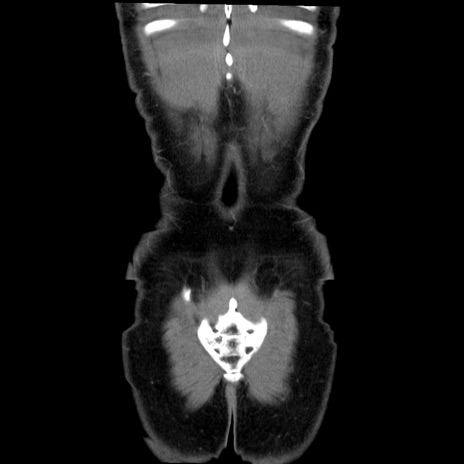

症例36(冠状断像)

【症例】20歳代 男性

【主訴】心窩部痛

【現病歴】今朝より上腹部痛あり。一旦軽快していたが再度出現したため救急要請。昨日夕に白身の魚を含む刺身を食べた。

【身体所見】BP 136/89mmHg、HR 74/min、BT 37.0℃、腹部:膨満、軟、心窩部に圧痛あり。反跳痛なし、筋性防御なし、腸雑音やや亢進あり。

【データ】WBC 17700、CRP 0.48